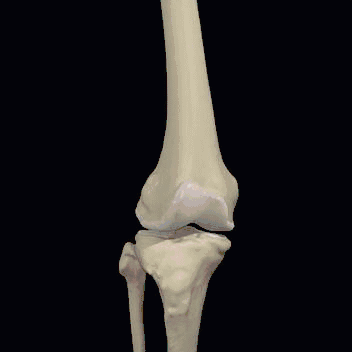

膝关节是人体最大、最复杂的关节,它仅仅靠一个狭小的接触面支撑着我们整个身体的重量。